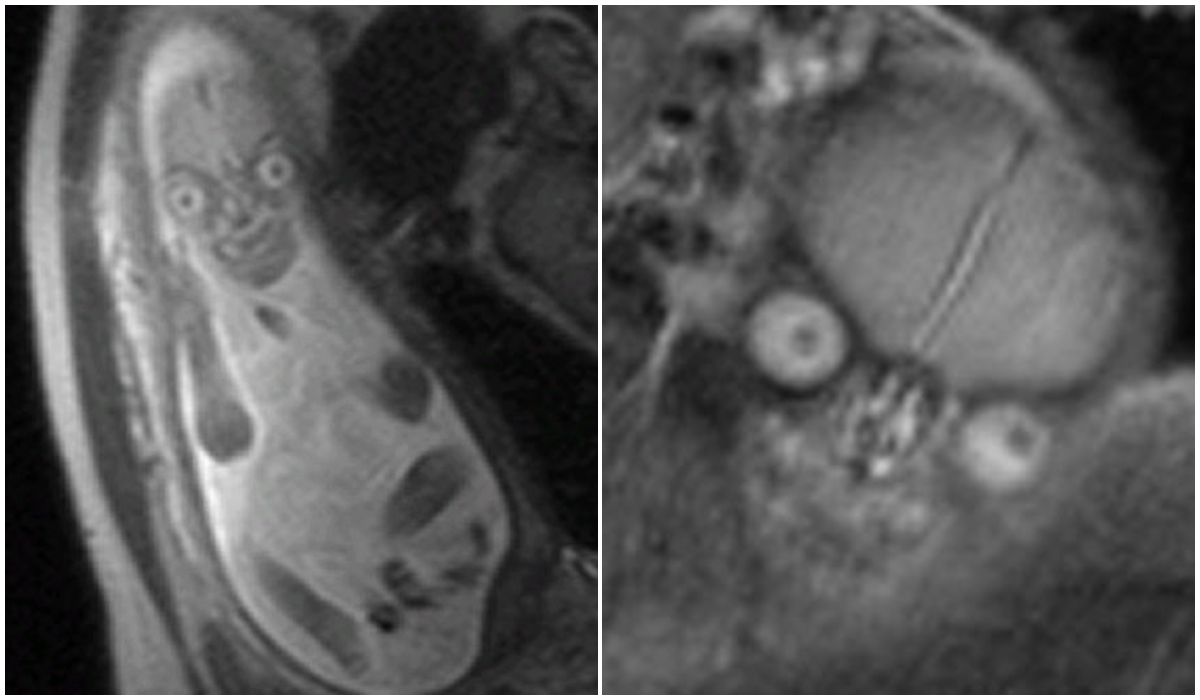

Spre deosebire de ecografia simplă, scanarea RMN oferă o imagine foarte diferită care adesea îi poate lăsa puțin șocați pe neinițiați.

Micuții din pântece arată de cele mai multe ori ca niște copii-demoni de pe altă planetă.

Imagini precum cele de mai jos devin adeseori virale pe rețelele de socializare, deoarece oamenii sunt cu adevărat îngroziți că un copil ar putea arăta așa.

Cercetătorul Jason Moody folosește tehnologia RMN pentru a studia modificările creierului legate de vârstă și le-a spus jurnaliștilor de la Snopes că aceste imagini "cu aspect diabolic" arată ce fac mai bine aceste aparate.

„RMN-ul ne ajută să diferențiem diferitele tipuri de țesut moale găsite în corp și noi suntem în mare parte țesut moale. Amintiți-vă, suntem în mare parte apă”, a spus Moody.

„Una dintre caracteristicile principale ale acestor imagini este diferențele substanțiale de semnal între ochi, creier, nas și restul feței.”

Un aparat RMN „folosește câmpuri magnetice și unde radio” pentru a face o mulțime de imagini în secțiune transversală ale corpului.

Scanarea le oferă medicilor și părinților o idee bună despre modul exact în care arată copilul.

Un RMN ar putea fi comandat pentru făt pentru a „evalua anomaliile din creierul, coloana vertebrală și corpul copilului”, potrivit Spitalului de Copii din Philadelphia.

Concluzia specialiștilor: dacă așteptați un copil și medicul spune că aveți nevoie de o scanare RMN, nu fiți șocați când bebelușul va arăta în imagini ca un extraterestru.